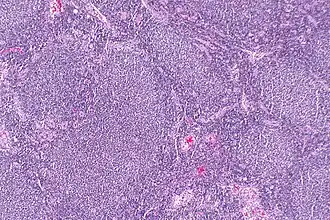

Linfonodo com linfoma folicular com a formação de "folículos" que lhe é característica.